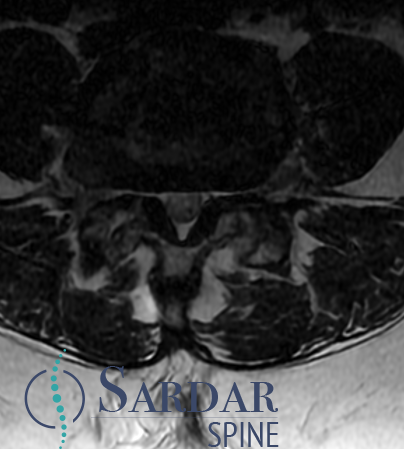

What would your surgical plan be for this patient with a cervical epidural abscess and severe arm weakness? #neurosurgery #physicaltherapy #chiropractor #spine #spinehealth #spinesurgery #cervicalspine

I performed a partial C4 corpectomy with fibular allograft -Abscesses can be more solid than expected -Partial corpectomy offers excellent decompression + stability -Material choice (titanium/allograft/autograft) matters less than thorough I&D and stabilization #cervicalspine